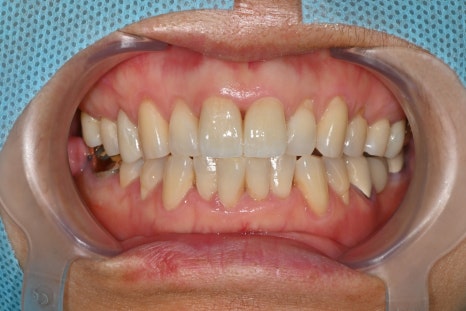

Front tooth crown treatment performed

Front teeth that receive a strong impact may develop fracture lines, discoloration, or changes in shape.

The patient’s tooth shape and function changed after the trauma,

so final treatment was completed with a zirconia crown.

has strengths in naturally matching the color, shape, and length of front teeth.

After the final crown placement, the patient said

it was good to be able to smile naturally like before

the lip scar also healed neatly and well